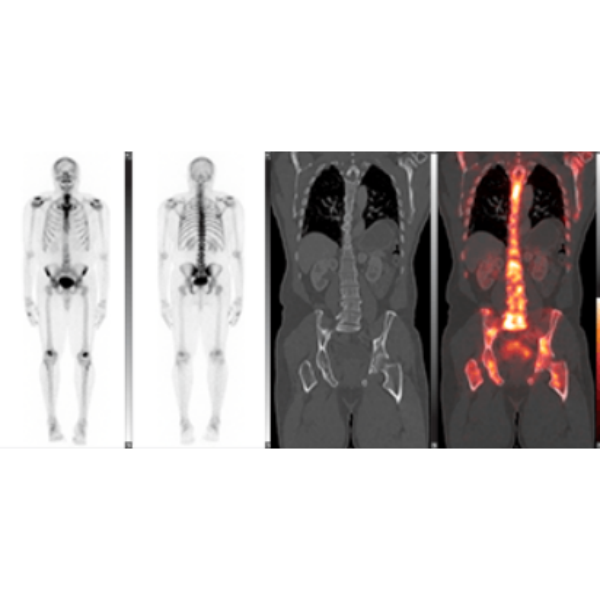

Quantitative Image Guidance

- Enables clinicians to make decisions with confidence.

- LesionID® supports the calculation of total tumor burden as well as individual statistics based on user-customizable cut-off criteria including PERCIST.

Advanced Therapy Response Tools

- Native support for Metabolic Tumor Volume, Total Lesion Glycolysis, and SUVpeak.

- Save time and add valuable information into your report.